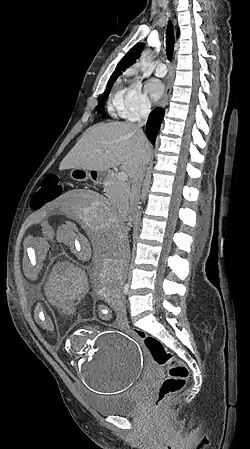

Medical imaging in pregnancy may be indicated because of pregnancy complications, intercurrent diseases or routine prenatal care.

MRI is commonly used in pregnant women with acute abdominal pain and/or pelvic pain, or in suspected neurological disorders, placental diseases, tumors, infections, and/or cardiovascular diseases.[3] Appropriate use criteria by the American College of Radiology give a rating of ≥7 (usually appropriate) for non-contrast MRI for the following conditions: